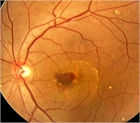

1. 滲出型加齢黄斑変性(AMD)に対する抗VEGF薬治療の維持期管理では、OCTによる検査結果をもとに再投与の判断を行ってよい。フルオレセイン蛍光眼底造影検査は必ずしも必要ない(推奨度1)